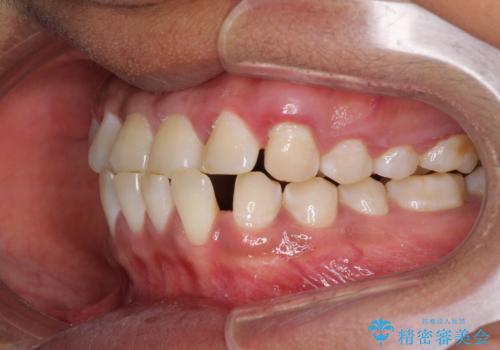

反対咬合の改善 途中で出産をしながらワイヤー矯正

- 前歯の隙間と反対咬合を気にして来院された患者様です。

マウスピース矯正も提案しましたが、しっかりと使用する自信がないとのことで、ワイヤー装置により矯正治療を行うこととしました。

咬合力が強く、反対咬合の改善に時間がかかりましたが、その後はスムーズに進めることができました。

途中、妊娠と出産があり、治療が中断したため、治療期間は延びましたが、出産も矯正治療も無事に終えることができました。